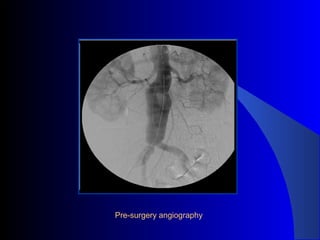

The document discusses the clinical application of the Endurant stent graft system in treating aorto-bisiliac aneurysms, detailing procedures performed on two male patients aged 72 and 73. Each patient had a history of dyslipidemia and carotid atherosclerosis, with procedures involving the bilateral bell bottom technique and the use of coils and fibrin glue. It includes pre-surgery imaging, intrasurgery angiography, and follow-up control scans to monitor outcomes.